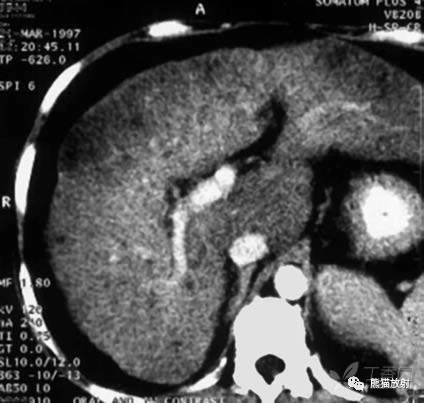

肝内多发低密度小结节